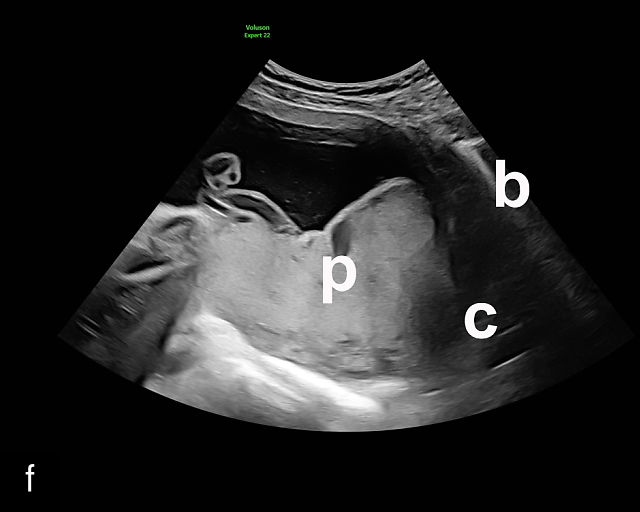

In the past, placenta previa was classified as complete, partial, marginal or low-lying.50,61 However, with advancements in ultrasound technology allowing precise assessment of the relationship between the placenta and the internal cervical os, the classification has been simplified.67 Placenta previa now refers to cases in which the placenta overlies the internal os to any degree, while low-lying placenta describes cases in which the lower placental edge lies within 2 cm of the internal os (Figure 5).51,66,67

5

Placenta previa and low-lying placenta. (a) Transabdominal grayscale ultrasound image suspicious for placenta previa. The placenta (PL) appears to overlie the internal cervical os (CX). Note the time stamp: 2:19:37. (b) Transvaginal ultrasound of the same patient taken approximately 50 minutes later. Note the time stamp: 3:10:25. The internal os and the lower placental edge are both clearly seen, and the placenta does not overlie the internal os. Because the lower placental edge is 1.93 cm from the internal os, it will likely resolve by the third trimester. (c) Transabdominal grayscale ultrasound of placenta previa. The placenta (p) covers the cervix, but the cervix, especially the internal os, cannot be visualized due to shadowing. (d) Transabdominal grayscale ultrasound of placenta previa. The placenta (p) covers the cervix (c) but shadowing obscures adequate visualization. The internal os is indicated by the arrow. (e) False-positive image of placenta previa on transabdominal grayscale ultrasound. The bladder (b) is full, pushing the anterior and posterior walls of the lower uterine segment (ls) together making it appear that the placenta (p) overlies the internal os of the cervix. In reality, the line depicted by the arrowheads is where the anterior and posterior walls of the lower segment are in proximity to each other. The cervix is much lower and is obscured by shadowing (c). (f) Transabdominal grayscale ultrasound image of placenta previa. The placenta (p) covers the cervix (c), but the cervix, especially the internal os, cannot be visualized due to shadowing. b, bladder. (g) Transvaginal grayscale ultrasound image of placenta previa. The placenta (p) completely covers the internal os (arrow) of the cervix (c). The internal os can be seen clearly. h, fetal head. (h) Transvaginal grayscale ultrasound image of posterior low-lying placenta (p). The lower placental edge is clearly seen and is 1.56 cm from the internal os (arrow) of the cervix (c). The placental edge and the internal os are clearly seen. h, fetal head. (i) Transvaginal grayscale ultrasound image of a posterior placenta previa (p). The internal cervical os is clearly seen (arrow). c, cervix. (j) Transvaginal grayscale ultrasound image of an anterior placenta previa (p). The internal cervical os is clearly seen (arrow). c, cervix; h, fetal head. (k) Transvaginal grayscale ultrasound image of a posterior placenta that was thought to be low-lying on transabdominal sonography but could not be adequately assessed. This examination clearly shows the lower edge of the placenta (p) to be 2.18 cm from the internal os (arrow) of the cervix, firmly establishing that the placenta is not low-lying and allowing the patient to undergo labor safely and deliver vaginally. c, cervix. (l) Transvaginal grayscale ultrasound image of placenta previa. The placenta (p) completely covers the internal os (arrow) of the cervix (c). The internal os can be seen clearly.

Most cases of placenta previa will be suspected prenatally by transabdominal ultrasound.49 However, this approach has several limitations and may be inaccurate.72,73,74 because the relationship between the placenta and the internal cervical os may be difficult to assess by transabdominal ultrasound.72,73,74 The bladder may be full, pushing the anterior and posterior walls of the lower uterine segment together, falsely creating the impression of a placenta previa (Figure 5e).61 There may be considerable shadowing, including by the fetal presenting part, which may limit the accuracy of transabdominal ultrasound (Figure 5d,f).75 Posterior placentas may be more difficult to assess.

Transvaginal ultrasound overcomes these limitations (Figure 5g–l).72,73,74,76 The probe is inserted into the vagina and therefore is closer to the region of interest.51,61 In addition, transvaginal transducers have higher frequencies and superior resolution compared to transabdominal transducers. Transvaginal ultrasound is safe and is not associated with increased bleeding.72,73,74,75,76 As such, transvaginal ultrasound should be the imaging modality of choice whenever there is suspicion of placenta previa.49,67,77